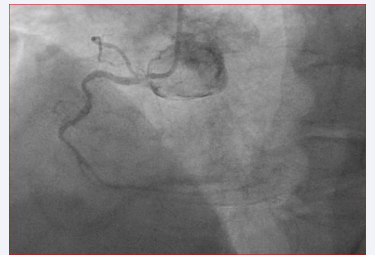

The patient is a 73-year-old male with a history of coronary artery disease (CAD), with a previous anterior myocardial infarction status 10 years ago. At that time he underwent primary coronary angioplasty with a drug-eluting stent placement on left anterior descending coronary artery. Three months ago he complained of angina and underwent a stress myocardial scintigraphy which demonstrated a large reversible defect involving the antero-septal and inferior wall. Coronary angiography demonstrated an 80% proximal left anterior descending coronary artery stenosis as well as restenosis of the previous stent in the middle part of left anterior descending coronary artery and 90% in the proximal left circumflex and critical ostial lesion involving the right coronary artery (Figure 1).

Figure 1: Ostial right coronary artery stenosis involving the origin of sinus node artery with poor visualization of its distal part due to blood supply impairment.

On the contrary, in our case an IAB was observed while patient was in the late phase after CABG intervention (30 days). In this patient the sinus node artery originated from the proximal tract of right coronary artery. A critical ostial right coronary artery stenosis which involved the origin of sinus node artery preoperatively was also observed. It is also well known that right-sided grafts are usually connected to the distal right coronary artery or posterior descending artery. So, arterial blood supply to the sinus node artery may not be affected with this type of revascularization technique. According to the previous study of Saremi et al. [22], in this case the distal part of sinus node artery (Figure 1) was less visualized due to the chronic impairment of blood supply. We hypothesised that late IAB presence on EKG one month after CABG, may be due to a persistent Bachman bundle blood supply impairment. Moreover, previous studies reported that patients developing AF after surgery have preoperatively increased intra-atrial conduction times (longer signal-averaged P-wave duration) [24], and more profound atrial structural changes like fibrosis [25,26] compared with patients who maintain sinus rhythm after surgery.